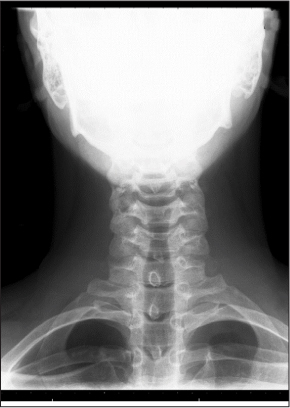

Anteroposterior View. The spinous processes should form a straight line, and the laryngeal and tracheal air shadows should be midline. Verify the regular outline of the lateral masses, and view the pedicles end-on to check for fracture. The spinous processes should form a straight line down the middle of the vertebral body and should be equidistant apart. If one spinous process is out of line with the others, a jumped facet may be present. (See Figure 3C.)

Figure 3C: Anteroposterior View